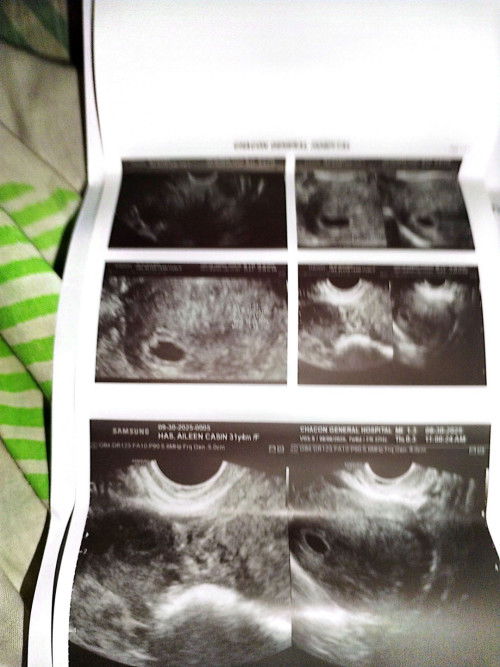

No heartbeat 6 weeks and 1day transvaginal ultrasound pero lmp ko sa clinic 7 weeks and 5 days

Babalik ako this coming October 21 para sa second transvaginal ultrasound para makita na kong meron na heartbeat si baby